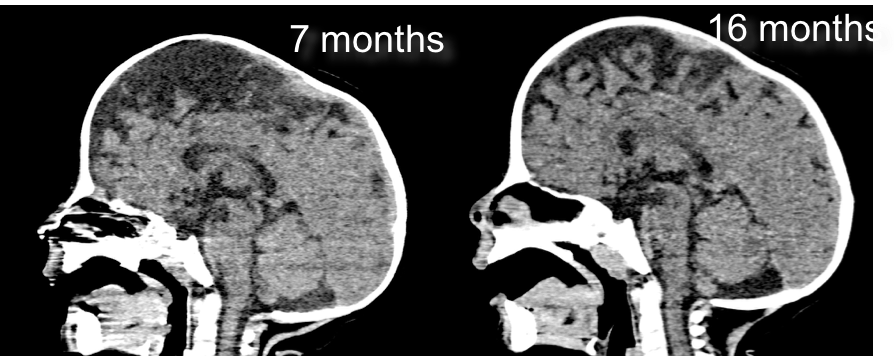

diagnostic tardif

dans les formes avec retentissement morphologique modéré, le diagnostic peut être fait tardivement devant des complications.

lorsque le diagnostic est tardif, il existe souvent d’emblée une HTIC et/ou un engagement tonsillaire ; ceci atteste du potentiel compressif de la scaphocéphalie.